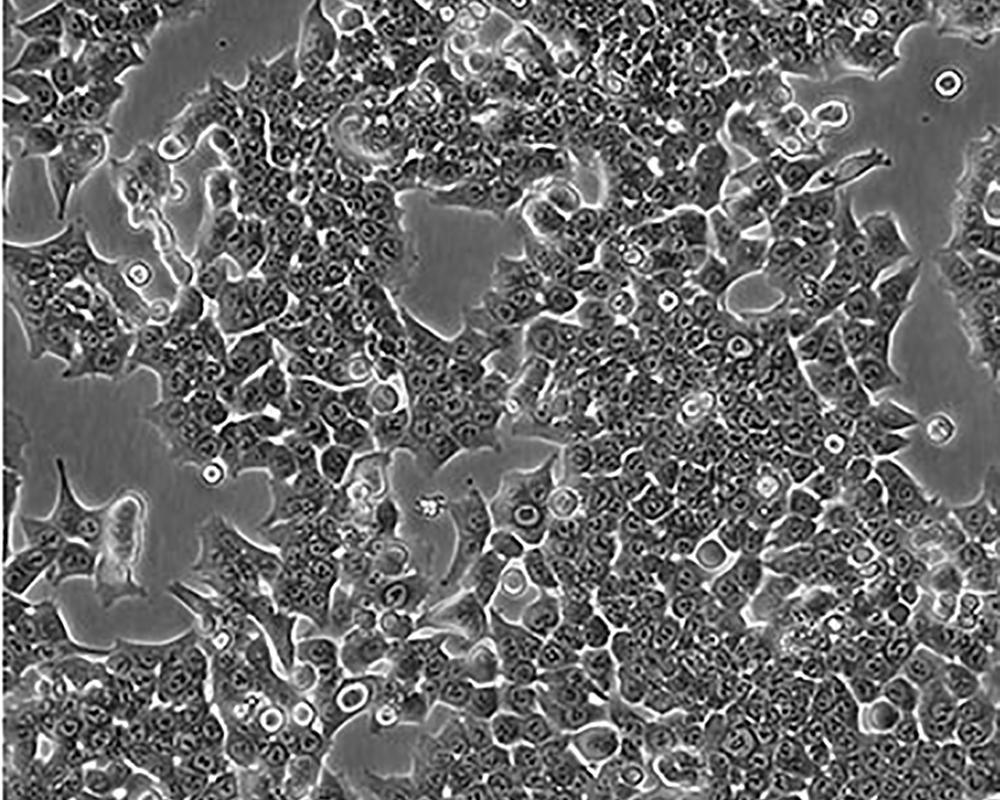

HCT 116

中文名稱 人結直腸腺癌細胞

組織來源 結腸腺癌;男性

生長特性 adherent

形態特征 epithelial

細胞描述 The cells are positive for keratin by immunoperoxidase staining.HCT 116 cells are positive for transforming growth factor beta 1(TGF beta 1) and beta 2(TGF beta 2) expression.